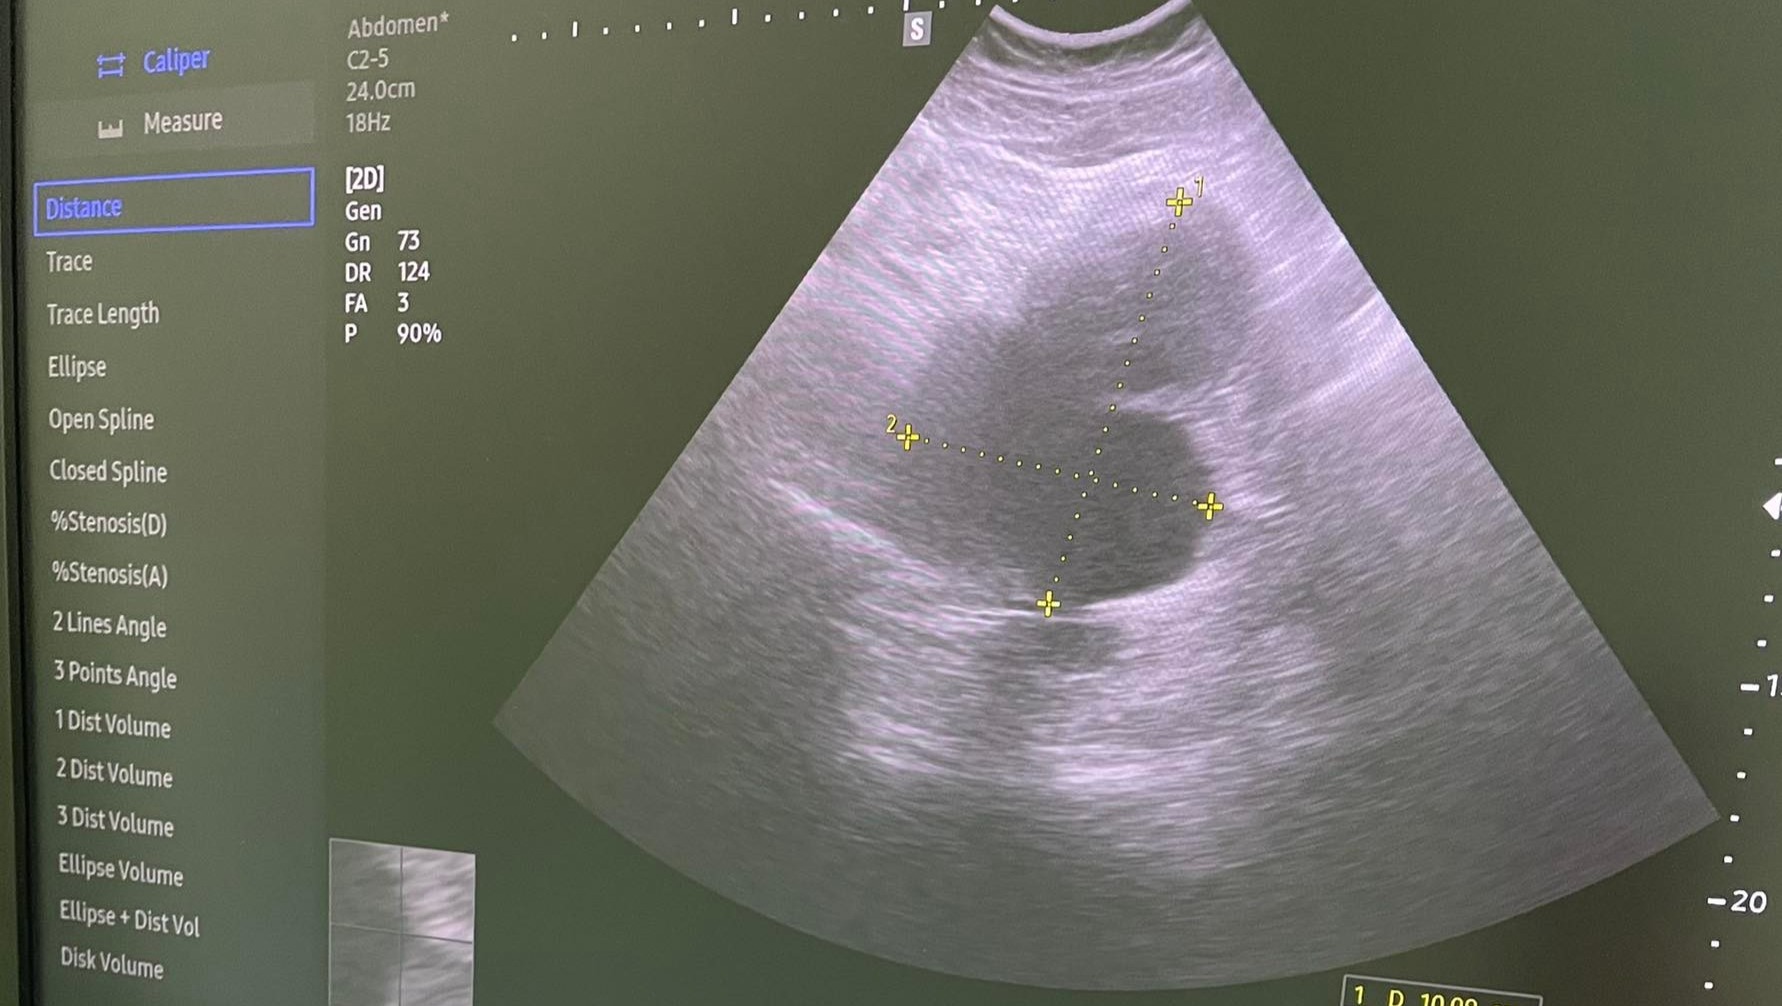

After many months of increasing pain, it's been discovered that there is a large chocolate cyst, and multiple tumors within the reproductive organs. While likely not cancerous, they nearly doubled in size in little over a month-- causing unimaginable pain daily. The pain disrupts her ability to work without interruption at work, be physically active on free days, and even eat and sleep.

(Photo above is the latest sonogram of the chocolate cyst-- the alien-looking thing was once one round boi, but within a month, has become like a... conjoined twin-like cyst. It was originally the size of a small orange and is now about the size of a big mango. It continues to grow at a fast rate.)

付けた超音波検査の写真は赤ちゃんではなく、左側の卵巣に付いているチョコレート嚢胞です